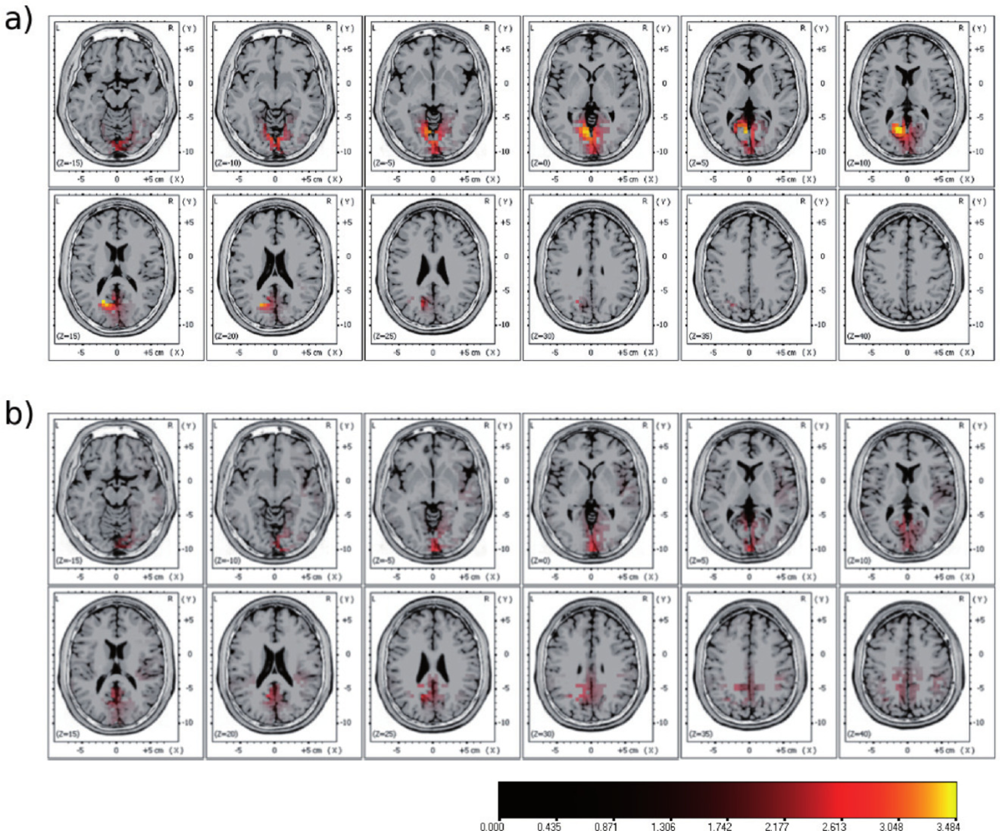

2.3. Multi-Modal Integration of MRI, fMRI, and Slow Cortical Potentials (SCP, DC-EEG)

Functional brain imaging: